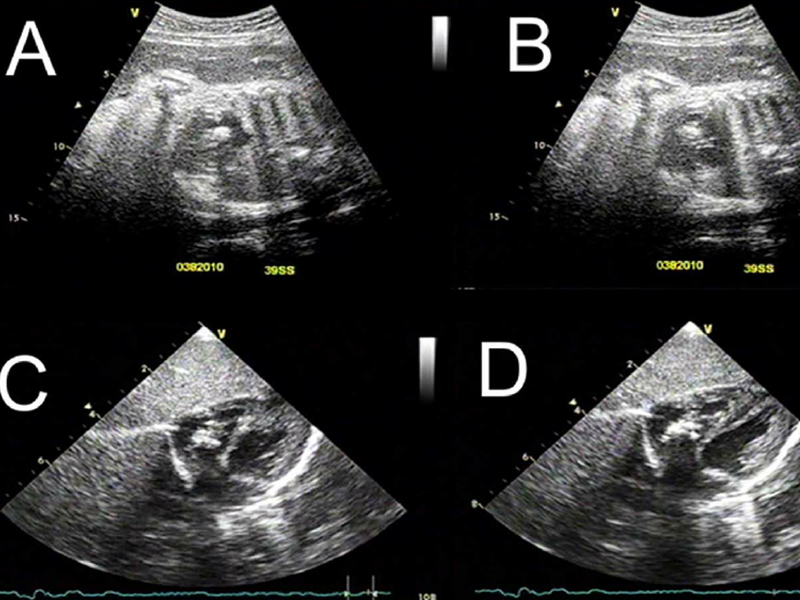

Fetal Echo